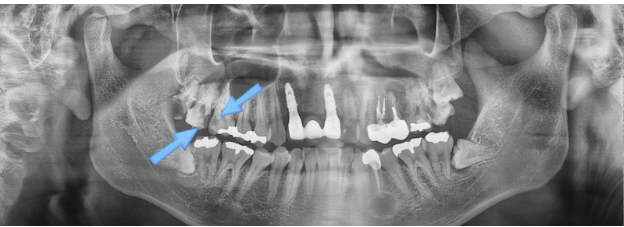

사진을 보면, 이전에 신경치료를 받았던 앞니가 깨져서 치과를 찾으신 사례입니다.

치료 당시 오른쪽 위 치아에서도 충치가 발견되었지만, 환자분께서는 앞니만 치료받고 싶다고 하셨습니다.

앞니에 임플란트 시술을 진행한 뒤 몇 년이 지나, 통증이 심해져 불편함을 느끼며 다시 내원하신 상황입니다.